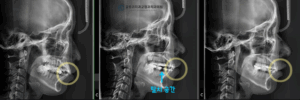

중랑구 교정치과 앞니가 삐뚤고 입이 나와보인다면? 발치교정을 통한 골격성 2급부정교합 개선 가능합니다.

안녕하세요, 교정과 전문의 김정은입니다. 앞니는 단순히 음식을 자르는 기능을 넘어 첫인상을 결정짓는 중요한 심미요소를 담당하는 부위입니다. 특히나 웃을때 제일 먼저 보이는 치아이기 때문에 조금만 앞니 삐뚤어있거나 돌출되어 있어도 얼굴 전체의…